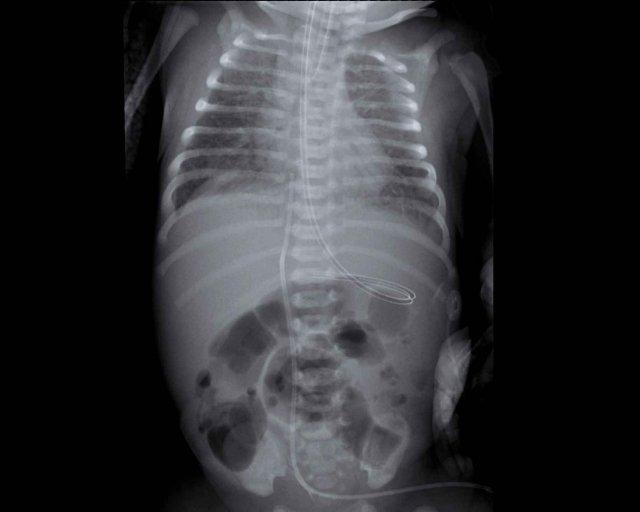

One day old neonate, 26 weeks of gestational age.

Image

- Granular opacification of both lungs.

- Vessels and cardiac silhouette are hard to distinguish.

- Umbilical venous line properly positioned.

- Vị trí đặt catheter động mạch rốn quá sâu, cần rút lại đến mức T6.

- NG tube in situ.

Conclusion: RDS grade 3.